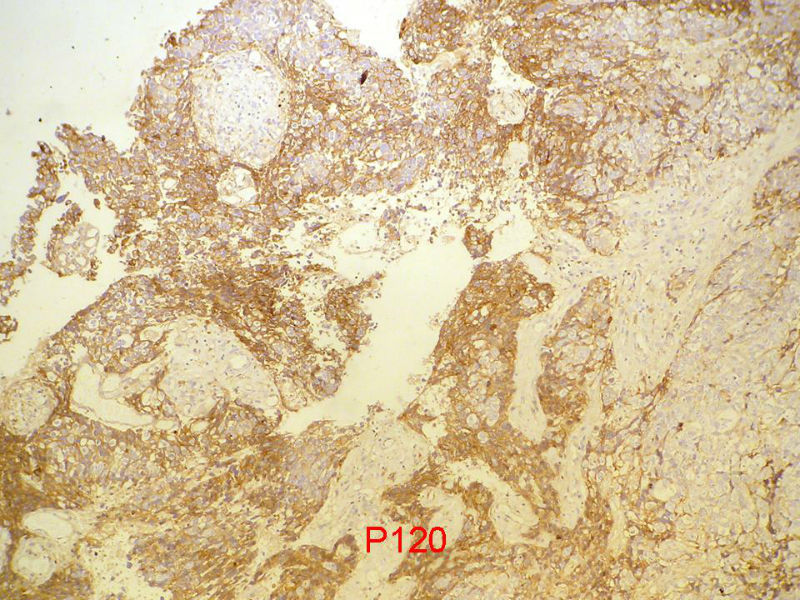

本例免疫组化结果:

ER(+), PR(+), HER-2(+), 没有采图。请判断E-ca是否阳性?